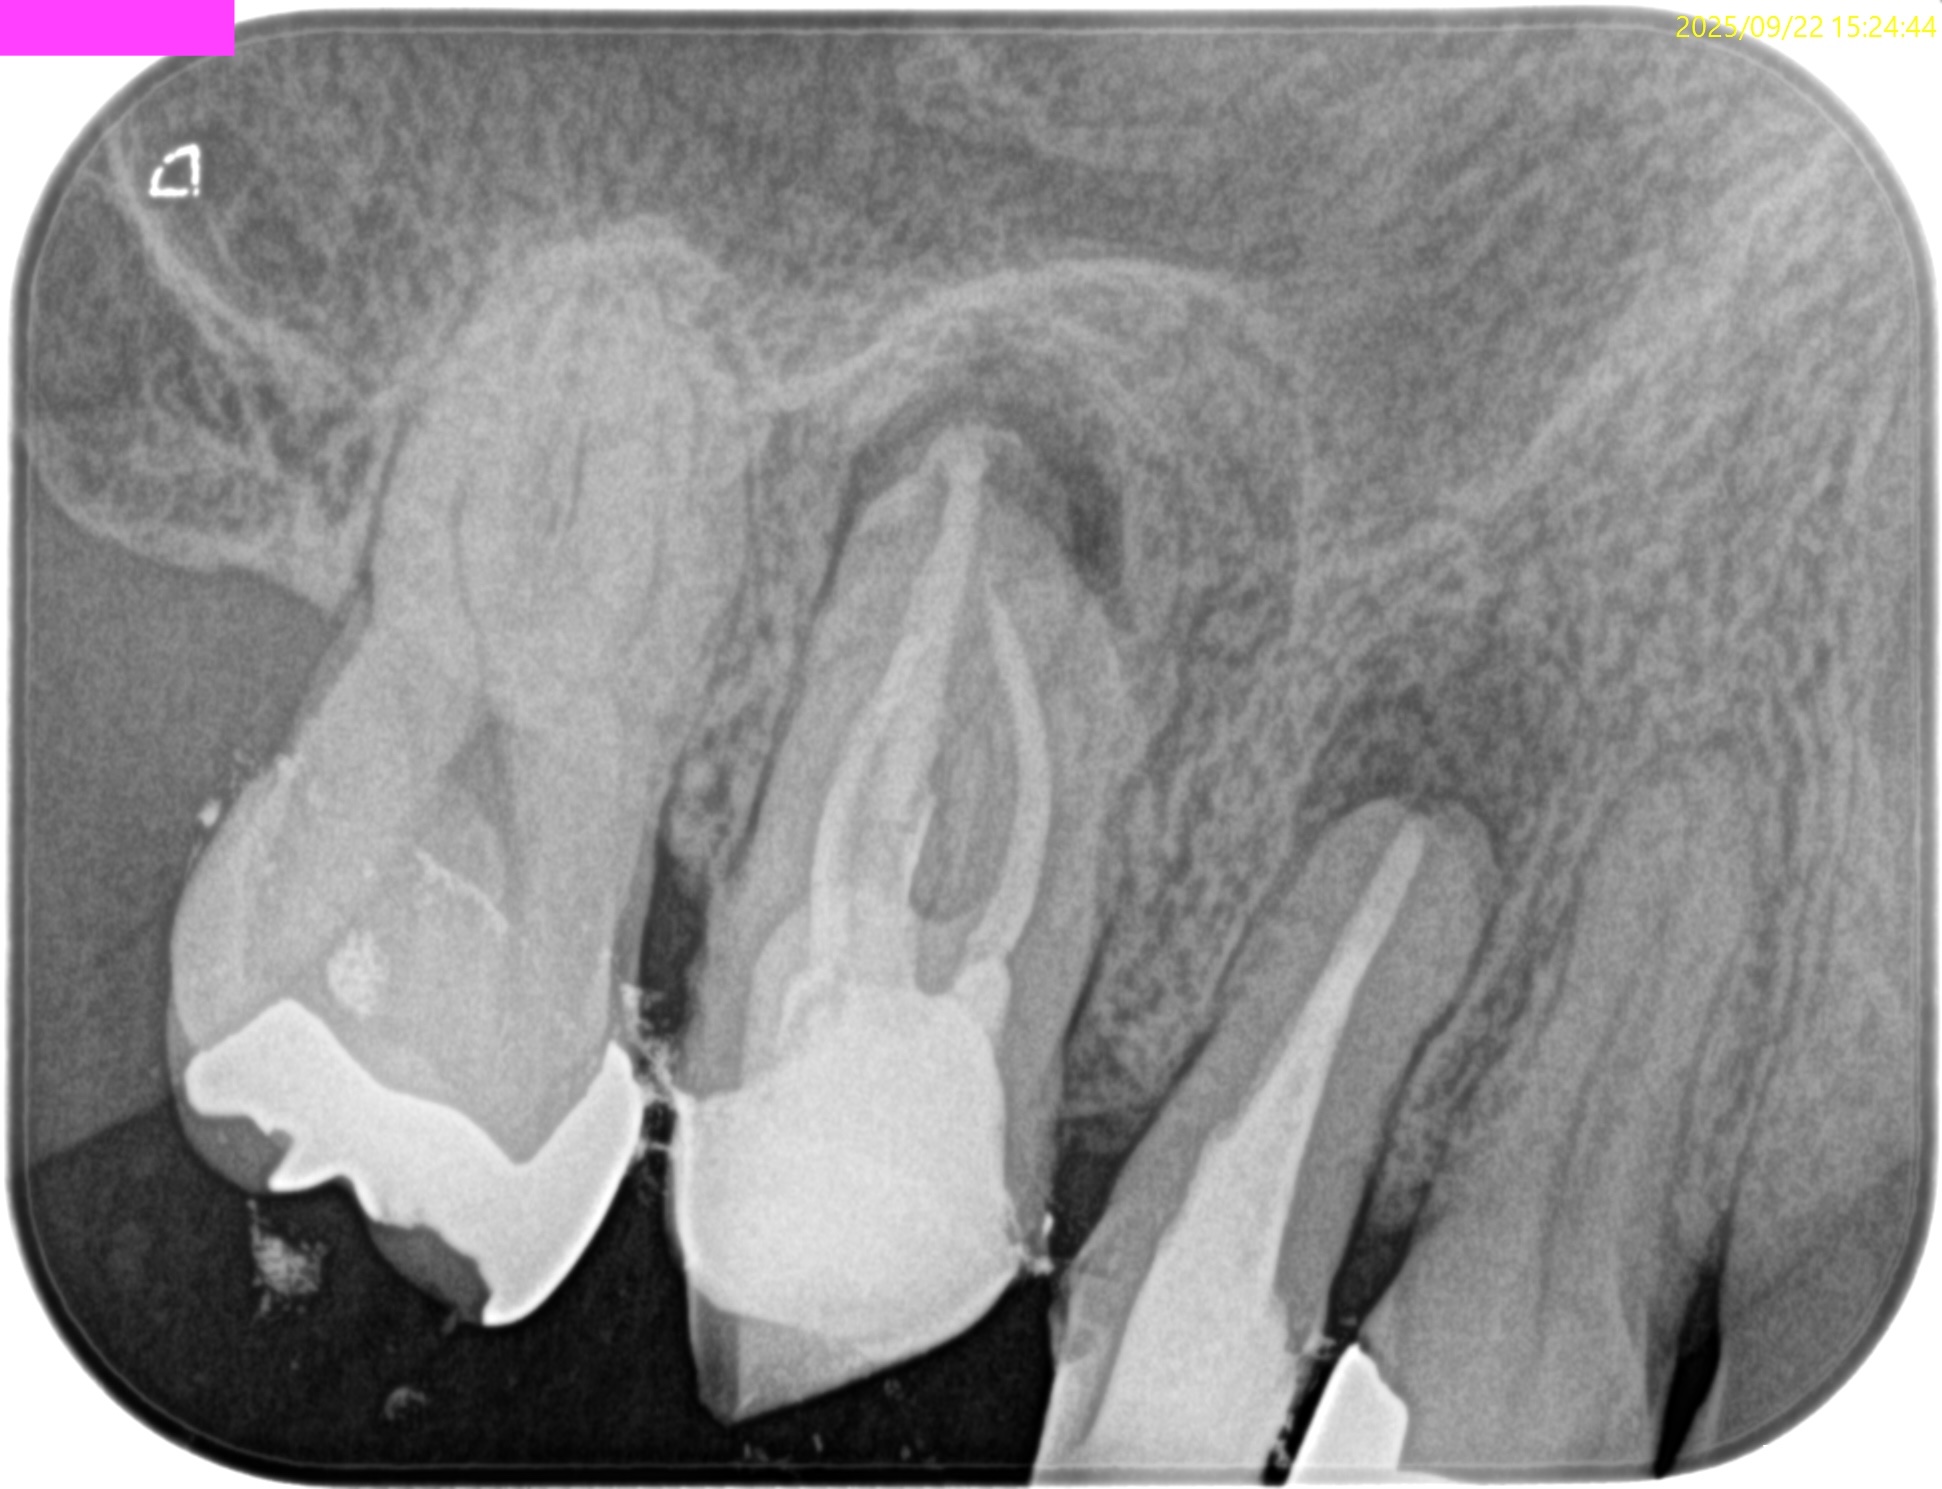

PA(2025.9.22)

これを治療した歯科医師は何もしていないに等しいだろう。

これで抜歯とは…

患者さんが疑念を持って正解だ。